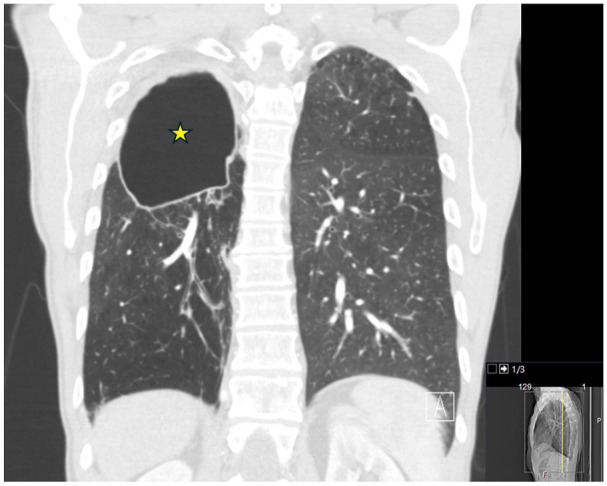

球孢子菌病是美国西南部的一种地方性疾病,可导致严重的肺部并发症,尤其是肺储备不良的慢性阻塞性肺疾病(COPD)患者。脓肿分枝杆菌易造成肺部结构性损伤,通常引起难以治疗的支气管扩张和空洞病变。我们报告一例58岁晚期慢性阻塞性肺病患者,30年前诊断为肺球虫菌病,入院前4年发现有脓疡分枝杆菌空洞性肺病的痰液和影像学证据,但未能随访。目前的表现是由于未经治疗的脓肿分枝杆菌感染的进展和潜伏的球虫感染的再激活。尽管开始进行抗真菌和抗生素治疗,但随后的过程因支气管胸膜瘘的发展和呼吸衰竭的恶化而复杂化,导致不利的结果。该病例强调了慢性阻塞性肺病患者并发感染的重叠临床和放射学特征以及破坏性结局相关的诊断挑战。及时的诊断检测和长期的综合治疗对于管理这种复杂的感染至关重要。

Coccidioidomycosis, endemic in the southwestern United States, can lead to severe pulmonary complications, particularly in chronic obstructive pulmonary disease (COPD) patients with poor lung reserves. Mycobacterium abscessus has a predisposition for structurally damaged lungs, commonly causing difficult-to-treat bronchiectasis and cavitary lesions. We present the case of a 58-year-old patient with advanced COPD and a remote history of pulmonary coccidioidomycosis diagnosed 30 years earlier, who was found to have sputum and radiographic evidence of M. abscessus cavitary lung disease 4 years prior to admission, but was lost to follow-up. The current presentation is attributed to the progression of untreated M. abscessus infection and reactivation of latent Coccidioides infection. Despite the initiation of antifungal and antibiotic therapy, the subsequent course was complicated by the development of bronchopleural fistula and worsening respiratory failure, leading to an unfavorable outcome. This case highlights the diagnostic challenges associated with overlapping clinical and radiologic features of concurrent infections and devastating outcomes in patients with COPD. Prompt diagnostic testing and prolonged comprehensive therapy are of paramount importance in managing such complex infections.